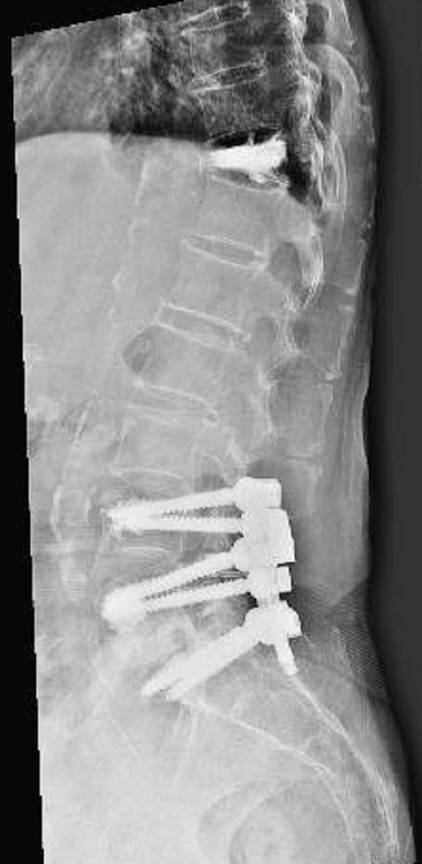

賴肇康說,邢奶奶骨質密度T值-4.2,是很嚴重的骨質疏鬆,胸椎骨折癒合不良,腰椎管狹窄及椎間盤突出、骨刺壓迫神經,造成坐骨神經痛。胸椎部分採微創手術以椎體千斤頂支架植入,再以骨水泥灌漿讓骨折復位,腰椎則進行微創減壓、椎間盤摘除、微創經皮穿刺及脊椎內固定融合術,手術後在加護病房觀察,隔天轉一般病房,再隔日已能下床活動,追蹤3個月,邢奶奶疼痛大幅改善,可以順利行走。

賴肇康指出,此個案棘手在於年齡過大、慢性病太多、骨鬆又嚴重,若採用傳統脊椎鋼釘手術,耗損老人元氣,也擔心骨釘零件鬆脫,產生併發症,最後以微創脊椎手術解決,傷口小恢復快。